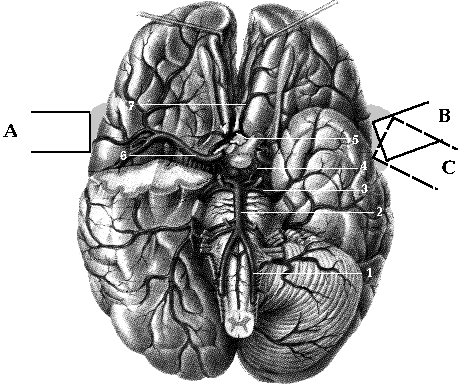

Внутренняя сонная артерия до входа в полость черепа ветвей не дает. Непосредственно после выхода из кавернозного синуса она отдает первую ветвь глазничную артерию, а затем делится на две конечные ветви - переднюю мозговую артерию и среднюю мозговую артерию (Рис 1.5).

Рис 1.5 Интракраниальные ветви

ВСА.

1- ОСА, 2- ВСА, 3- сифон ВСА, 4- ПМА, 5-

СМА.

Обе передние мозговые артерии отходят (чаще под прямым углом) от передней полуокружности внутренней сонной артерии в месте, соответствующем наружному краю перекреста зрительных нервов. Эти артерии направляются вперед и внутрь в продольную щель мозга над corpus сollosum. Диаметр передних мозговых артерий варьирует от 1.5 до 2.5 мм. Число и ход вторичных ветвей ПМА весьма вариабельны. Различают от 6 до 8 вторичных ветвей передней мозговой артерии. Корковые ветви передней мозговой артерии анастомозируют на поверхности мозга с корковыми ветвями средней и задней мозговых артерий.

Средняя мозговая артерия является непосредственным продолжением ВСА. Диаметр СМА варьирует от 1.9 до 3.2 мм. Пройдя несколько миллиметров, средняя мозговая артерия погружается в боковую щель. Протяженность основного ствола СМА (I сегмент СМА) различна и составляет от 5 до 30 мм. От первого сегмента СМА (MI) берут начало центральные артерии, идущие к коре больших полушарий, от них отходят вторичные, третичные и т.д. ветви. В бассейне СМА можно наблюдать ветви до седьмого порядка. Число центральных артерий, составляющих в совокупности MII сегмент СМА, колеблется от 4 до 10. Артерии третьего, четвертого и других более мелких порядков составляют MIII cегмент СМА (рис. 1.5).

Корковые ветви СМА широко анастомозируют с корковыми ветвями ПМА и задней мозговой артерии (ЗМА).